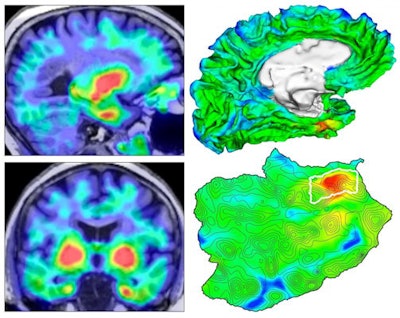

Four views of the origin of tauopathy in vivo. (Left) Tau PET images for a cognitively normal person. (Top right) 3D rendering of brain surface with tau PET overlay. (Bottom right) Flat map showing topographic detail of surface anatomy with tau origin identified in white outline. Images and caption courtesy of Justin Sanchez and Dr. Keith Johnson of MGH.

Four views of the origin of tauopathy in vivo. (Left) Tau PET images for a cognitively normal person. (Top right) 3D rendering of brain surface with tau PET overlay. (Bottom right) Flat map showing topographic detail of surface anatomy with tau origin identified in white outline. Images and caption courtesy of Justin Sanchez and Dr. Keith Johnson of MGH.What's more, they determined that a greater rate of tau spread was associated with baseline measures of both global beta-amyloid burden and median temporal lobe tau levels.